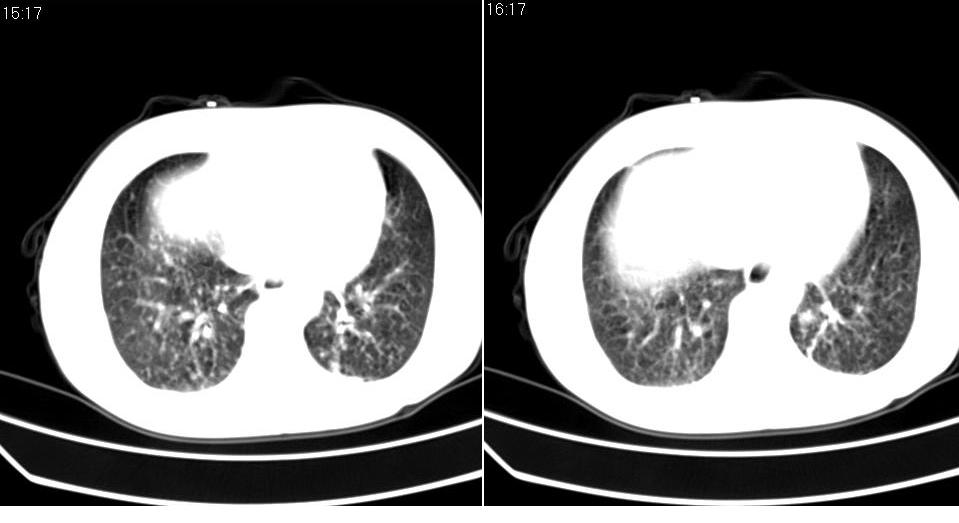

标题: CT16839:胸部CT平扫

女 50岁,在其他医院确诊肺癌.

肺癌并肺及纵隔转移

支持 右肺上叶肺癌并两肺及纵隔转移。

肺癌并肺内及纵隔淋巴结转移